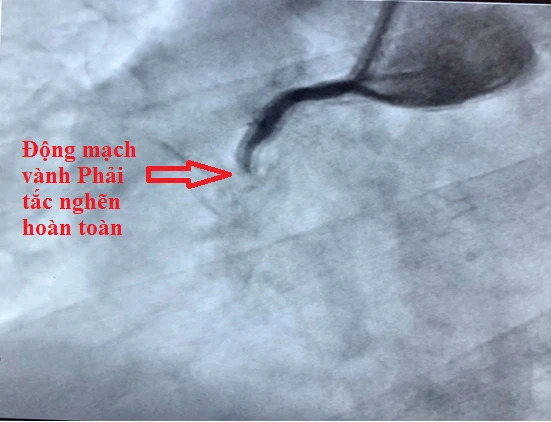

Hình ảnh động mạch mạch vành phải bị tắc nghẽn hoàn toàn của một bệnh nhân. Ảnh: BVCC

“Lúc nhập viện, cả hai bệnh nhân đều đau ngực dữ dội, vã mồ hôi, huyết áp và nhịp tim rất thấp, tính mạng bị đe dọa. Hai bệnh nhân được các bác sĩ trực cấp cứu thăm khám và chẩn đoán ngay bệnh lý nhồi máu cơ tim cấp nghĩ nhiều đến tắc nghẽn động mạch vành”, BS Tiến chia sẻ.

Sau xử trí đặt stent tái thông động mạch vành tắc nghẽn, hai bệnh nhân đã ổn định và xuất viện.